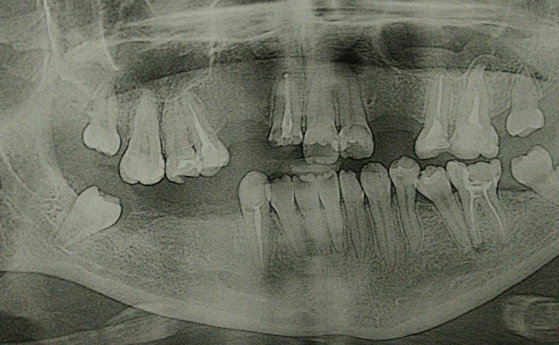

Добрый день. Любой отек — это воспаление, в вашем случае сложно точно без рентген-снимка диагностировать причину. В любом случае вам необходимо обратиться к стоматологу на предмет ревизии каналов с последующим лечением, а затем изготовить культевую восстановительную вкладку и коронку, так как коронковая часть зуба разрушена и восстановление пломбой уже невозможно.